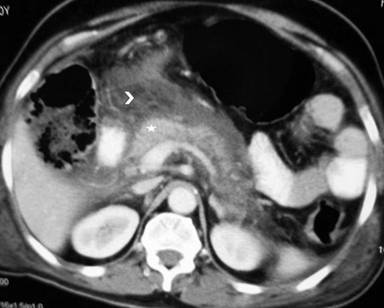

A 60 year old male, a diabetic for 5 years, was admitted with three days of abdominal pain associated with vomiting and complicated by altered sensorium for one day. The diagnosis of acute pancreatitis was made as patients had elevated serum amylase (1980 IU/L, Normal 60-180 IU/L) and computed tomography done on fifth day revealed diffusely bulky pancreas with evidence of peripancreatic necrosis and fluid collection (Figure 1). The patient was a non-smoker and non-alcoholic. He had been on Metformin 2 grams daily for previous three years and had no evidence of microvascular or macrovascular complication. His body mass index was 28.6 (overweight). The evaluation for aetiology was non-contributory: his serum triglyceride, calcium profile and intact parathormone levels and ultrasound abdomen for gall stones were non-contributory. The patient was shifted to intensive care unit and managed with fluid resuscitation and administration of inhalational oxygen for acute lung injury. Initially the patient had a Glasgow Coma scale score of 10 (E2V3M5). The muscle tone was normal, and deep tendon reflexes were normal and plantars flexor. Over next 24 hours the sensorium of the patient improved from the initial delirium to drowsy but arousable state. At this time the patient was noted to have asterixis (Video 1). The muscle tone was normal, bilateral plantars were flexors and the deep tendon reflexes remained normal. The workup for cause of asterixis including PaCO2 (34 mm of Hg), kidney function tests (blood urea: 34 mg/dL, normal: 8-42 mg/dL; serum creatinine: 0.7 mg/dL, normal: 0.3-1.3 mg/dL) and arterial ammonia levels (24 µmol/L, normal:11-35 µmol/L), electrolytes (serum Na: 139 mEq/L, serum K: 3.8 mEq/L, serum Ca: 8.9 mg/dL, serum phosphate: 3.8 mg/dL, serum Mg: 2.1 mg/dL) and blood sugars were normal (134 mg/dL). MRI of the brain was normal and the EEG revealed diffuse slowing of theta range consistent with diffuse encephalopathy. Examination of cerebrospinal fluid showed no white cells and normal sugars and proteins (74 mg/dL and 25 mg/dL, respectively). Asterixis improved over next three days. The patient had transient acute lung injury which improved over 48 hours and the patient was discharged after 20 days of hospitalisation.

Figure 1. Abdominal computed tomography showing an enhancing pancreas (star) with peripancreatic necrosis (arrowhead). |